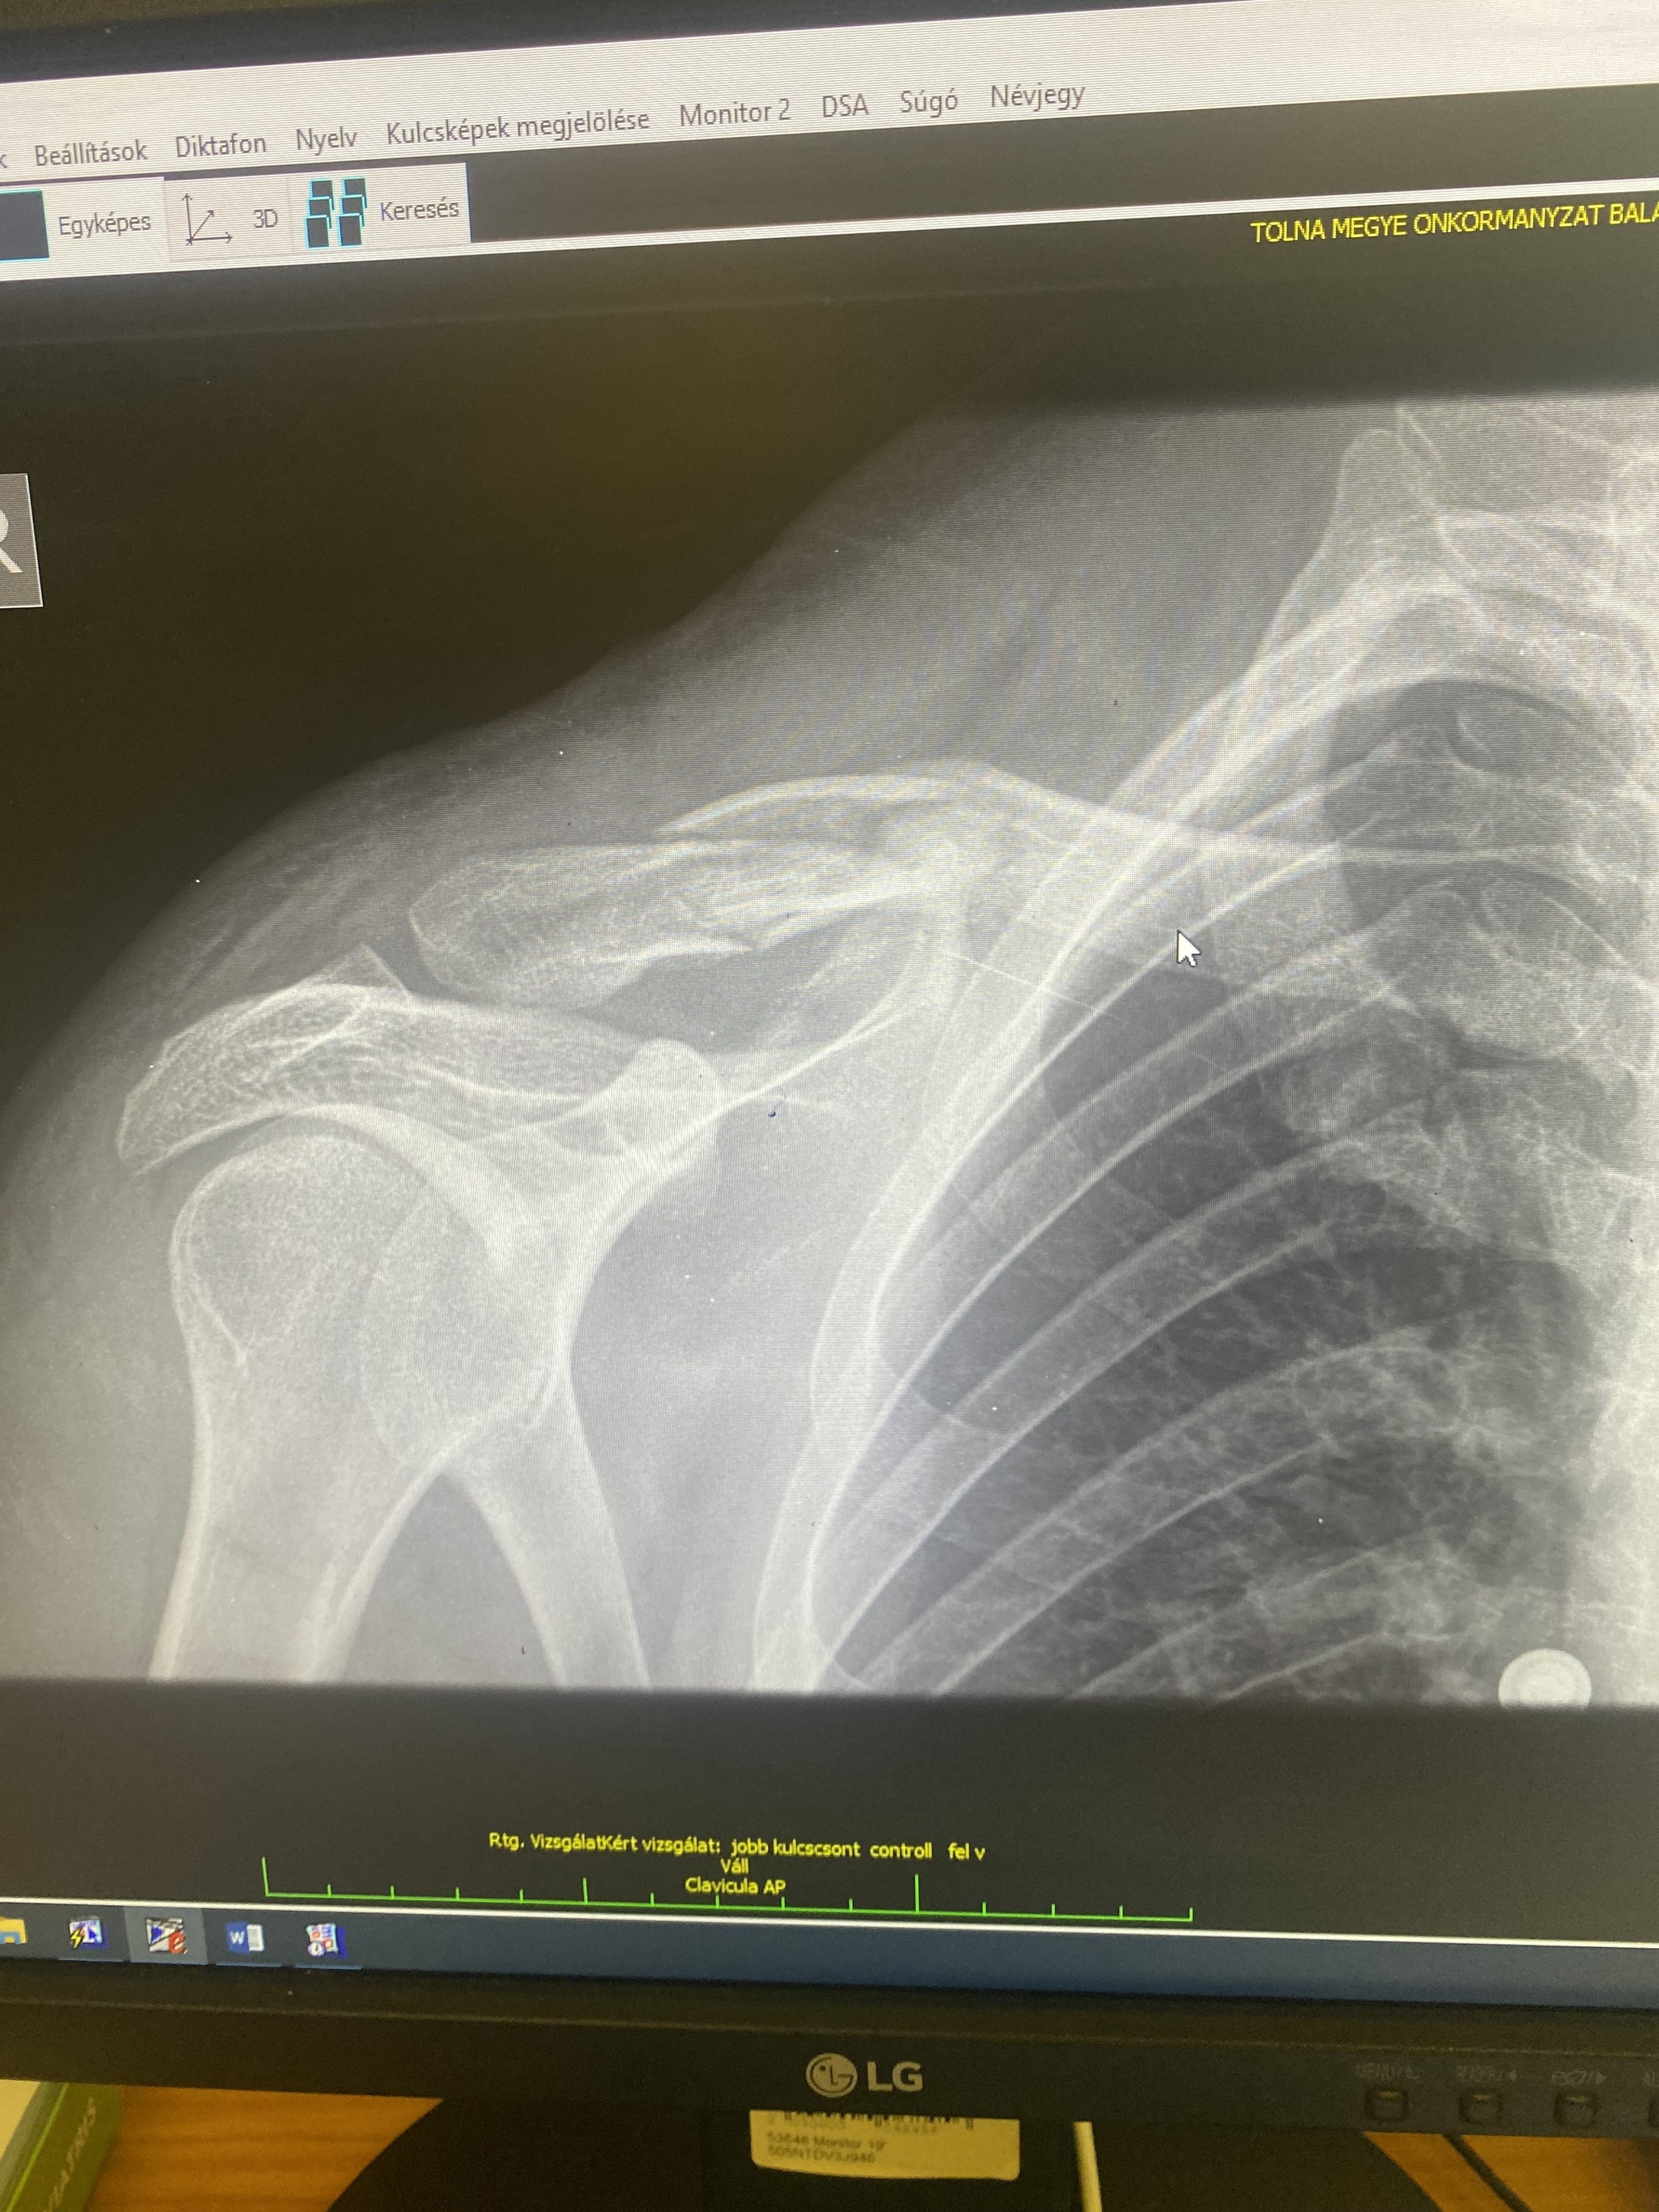

После падения было ощущение что это просто вывих и я сейчас съезжу к травматологу и он поставит все на места. По приезду в клинику (платную) мне сразу же сделали рентген.

Увидели перелом.

И вот собственно вопрос : Понимаю что рентген не просматривают врачи по фото монитора с телефона , подскажите на фото перелом со смещением? И нормально ли срастется кость с бандажом? Или все же на операцию настаивать?